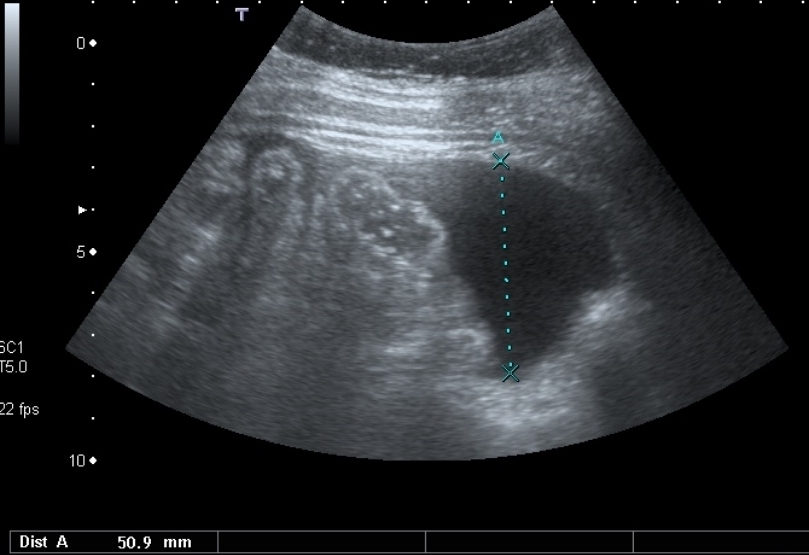

Vous hospitalisez dans le service où vous exercez Mme B., 32 ans, pour ascite. Cette patiente est d’origine guinéenne et ne vous déclare aucun antécédent hormis quelques accès palustres au pays. Elle ne travaille pas et est en situation irrégulière comme son mari et son fils de 6 ans avec qui elle vit. Elle présente depuis trois mois environ une altération de l’état général, et plus récemment des douleurs abdominales, une augmentation du périmètre abdominal et une prise de poids. Elle n’a aucune autre plainte.

Votre examen clinique retrouve : Température : 38,2°C, Pression artérielle : 123/65 mmHg, Fréquence cardiaque : 100 batt/min, SpO2 : 99% en air ambiant. L’abdomen est sensible dans son ensemble avec une matité déclive mais sans défense. Le reste de l’examen est normal, en particulier il n’y a pas de signe d’hypertension portale ou d’insuffisance hépatocellulaire.